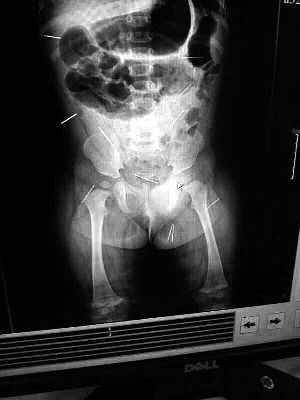

山東聊城11個月女嬰萱萱(化名)疑似被人以12根鋼針插滿臀部、腹腔等部位,昨天在兒童醫(yī)院會診后,醫(yī)生稱3根針靠近胸腔最危險,首批先行取出,預(yù)計將在下周二手術(shù)。孩子父母稱孩子一直由家人照顧,自家與他人并無冤怨。山東警方表示正在偵破中,不便透露案情。

“要不是當(dāng)初那幾個紅點,可能到現(xiàn)在我們還不知道孩子身體里有鋼針!”昨天,在兒童醫(yī)院住院處,萱萱爸爸范先生稱,日前原本很愛笑的萱萱突然變得有些焦躁,一抱起來就哭,孩子母親偶然間在萱萱屁股上發(fā)現(xiàn)了幾個小紅點兒,原以為是蚊蟲叮咬,就醫(yī)結(jié)果卻讓人不寒而栗?!搬t(yī)院拍出的片子上,萱萱的體內(nèi)有12根鋼針,插滿臀部、腹腔、骨盆等各個部位?!狈断壬榻B,因為鋼針已深入體內(nèi),要是孩子不哭鬧,他們很難發(fā)現(xiàn)。

北京晨報記者了解到,目前體內(nèi)的12根鋼針多分布在孩子的臀部,一根在腹部,其余3根在胸腔附近,其中一根很接近心臟。“因為孩子太小,醫(yī)生們害怕取針的時候?qū)λ斐蓚Γ谛厍桓浇?針可能會威脅她的生命”。

截至昨晚6時許,北京晨報記者從兒童醫(yī)院宣傳部門了解到,孩子目前已經(jīng)接受完專家會診,暫定今天和下周一進行術(shù)前檢查,如果一切順利將在下周二手術(shù),“孩子暫時沒有生命危險”。